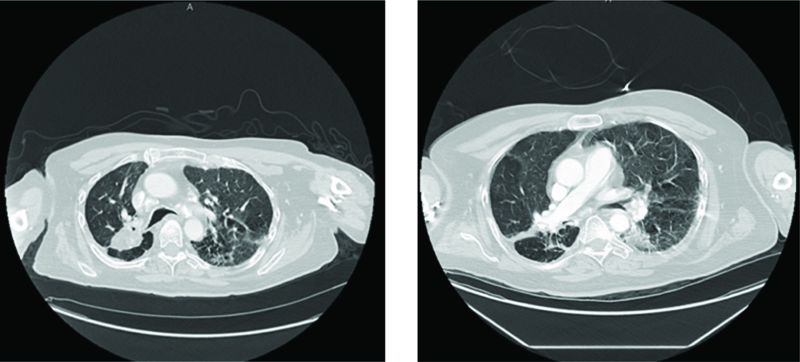

A 69-year-old man with a past medical history of intellectual disability due to prematurity at birth leading to blindness and deafness, asthma, tracheomalacia, seizure disorder, and GERD presented to the emergency room with shortness of breath associated with fever and coughing. This patient has a complex medical history, including multiple prior hospitalizations for recurrent aspiration pneumonia, swallowing dysfunction, and a lung mass. He had a percutaneous endoscopic gastrostomy tube placed seven years ago and does not have oral intake. His vital signs included 85% oxygen saturation on room air, tachycardic with a heart rate 120s beats per minute, and a temperature of 99.5°F. Laboratory results included leukocytosis, anemia, and thrombocytopenia. The patient appeared to be in respiratory distress and was started on high flow nasal cannula 20 liters per minute with a FiO2 of 60%. Computed tomography (CT) of the chest showed mixed perihilar and bilateral pulmonary densities (Figure 1). His previous CT chest from six years ago showed multiple tiny micronodules clustered and scattered throughout both lower lung fields that may be sequelae of granulomatous disease (Figure 2). The patient had a wedge resection lung biopsy twenty years ago that showed presence of lentil starch material in the bronchioles and multifocal foreign body giant cell reaction, subpleural calcified hyalinized nodules, and subpleural fibrosis, consistent with lentil aspiration pneumonia (Figures 3 and 4).

Figure 1

Figures 1A and B. CT chest with contrast showing advanced mixed perihilar and bilateral pulmonary densities with right perihilar bronchial thickening.